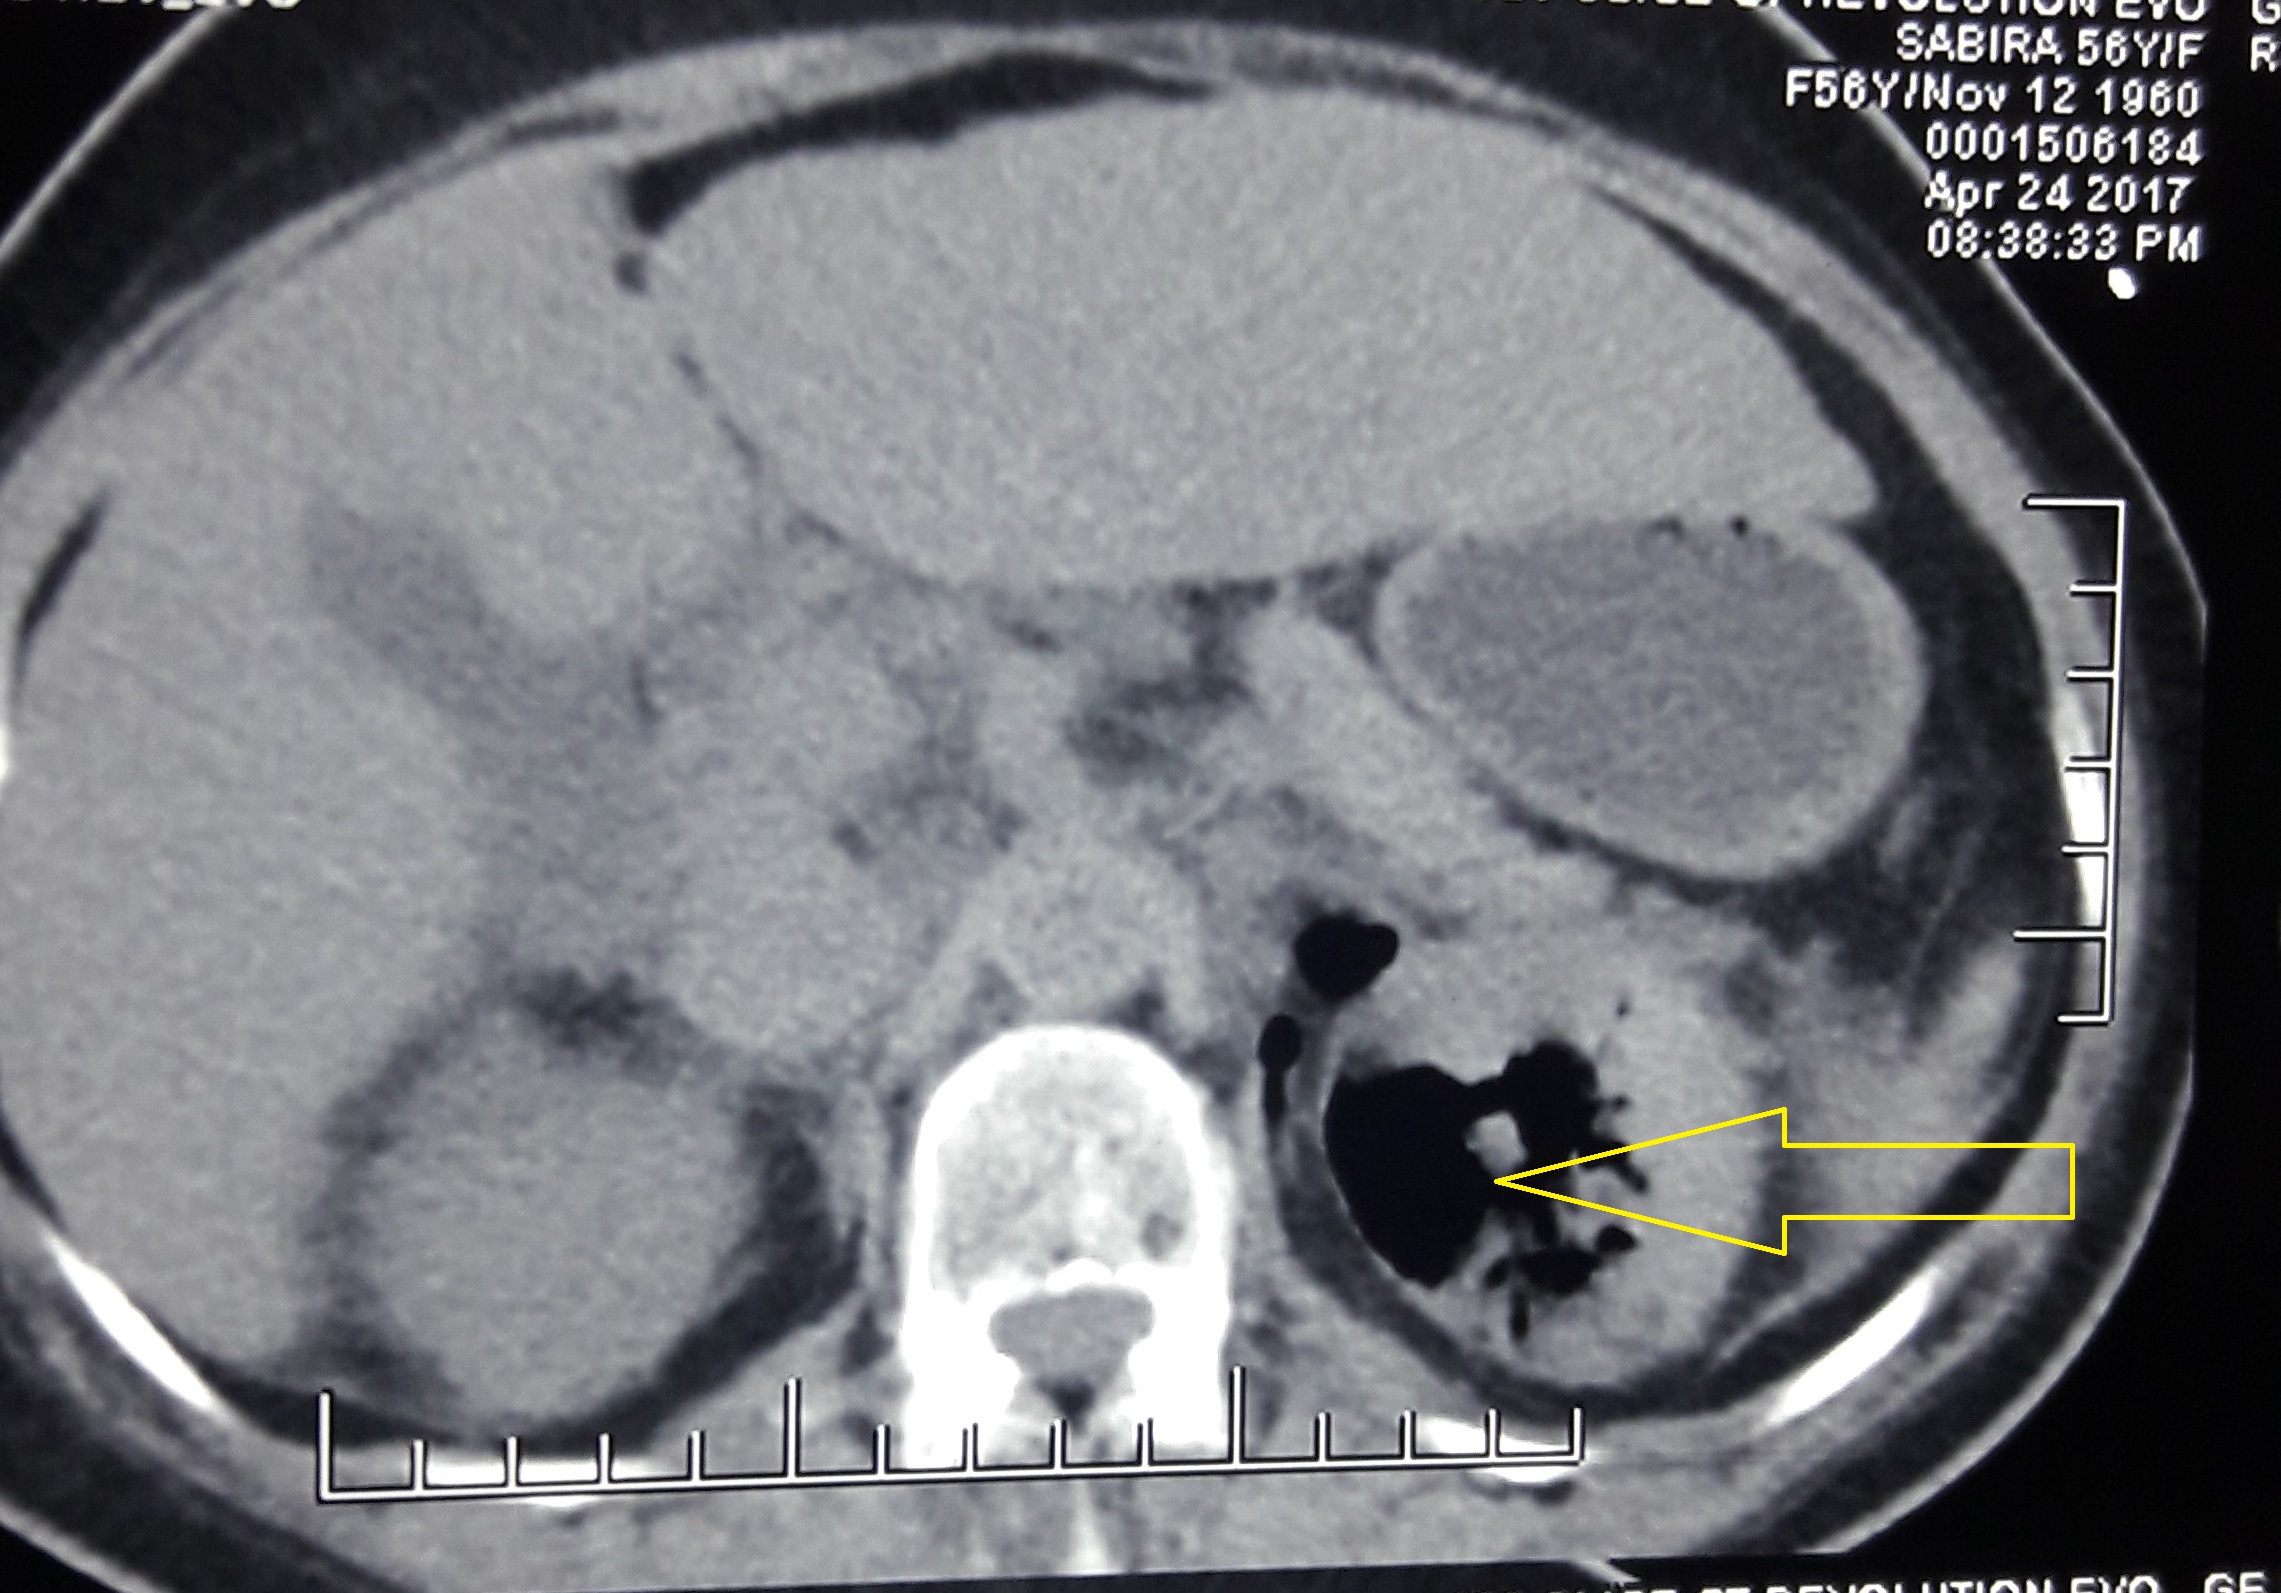

Emphysematous pyelonephritis is a life threatening acute necrotizing infection with associated gas formation involving the renal parenchyma and perinephric tissues. Dengue fever, according to the WHO, is the most rapidly spreading mosquito borne viral infection in the world. Dengue Hemorrgahic Fever is a more severe form of dengue fever and is characterized by fever, bleeding manifestations, plasma leakage and thrombocytopenia. This is a case of a 56 year old female, who presented with history of fever, headache, myalgia and dysuria; and was diagnosed to have emphysematous pyelonephritis with Dengue Hemorrgahic Fever. She was successfully managed with intravenous antibiotics and platelet transfusions, without any urological interventions.